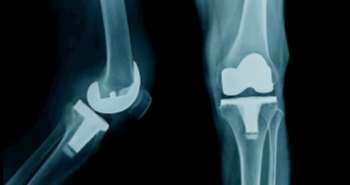

People using statins for more than five years and those using atorvastatin have a significantly lower chance of developing knee pain.

As per research published recently in the Arthritis Care & Research Journal, the patients who used statins for more than five years has considerably less risk of knee pain although their role in osteoarthritis (OA) management is still debatable.

Statins, HMG-CoA reductase inhibitors show various pleiotropic impacts, but their relationship with regards to knee osteoarthritis is inadequate. This study was conducted among the North American people to evaluate whether statins were associated with reduced risk of symptomatic radiographic knee OA (SROA), radiographic OA (ROA) and related pain or not. The analysis involved 4,448 patients from the Osteoarthritis Initiative. Self-reported information approved by a trained interviewer were utilised to define the use of statins. The study population was followed-up for four years. The incident ROA and SROA and knee pain worsening i.e., Western Ontario and McMaster Universities Osteoarthritis Index difference between baseline and each annual exam ≥14%) were taken as knee OA outcomes. A total of 1,127 patients used statins at the baseline. No association between statins and reduced risk of incident ROA and SROA and knee pain was noticed. Although, statins involved atorvastatin for more than five years was associated with a reduced risk of developing pain, but rosuvastatin, on the other hand, showed the opposite response. The adjustment for the propensity score validated the conclusions regarding statins at baseline, after treatment and five years after the procedure.